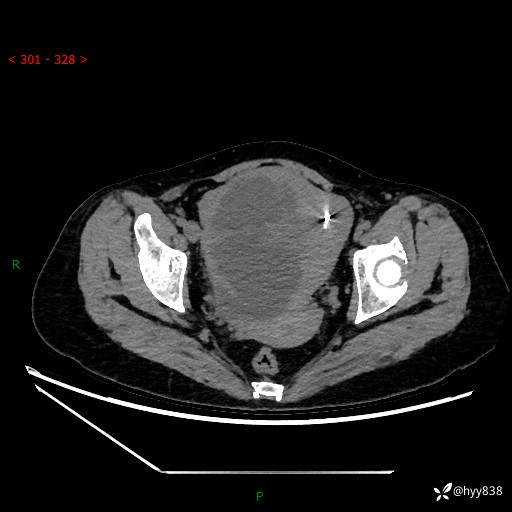

辅助检查:CT

盆腔CT平扫